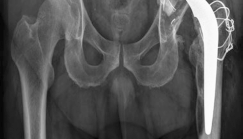

(Figs. 19.17, 19.18, and 19.19)

Fig. 19.17 Anteroposterior pelvis radiograph depicting a cemented total hip arthroplasty with eccentricity of the femoral head in the polyethylene liner

Diagnosis : Left total hip arthroplasty wear and aseptic loosening (Figs. 19.17, 19.18 and 19.19)